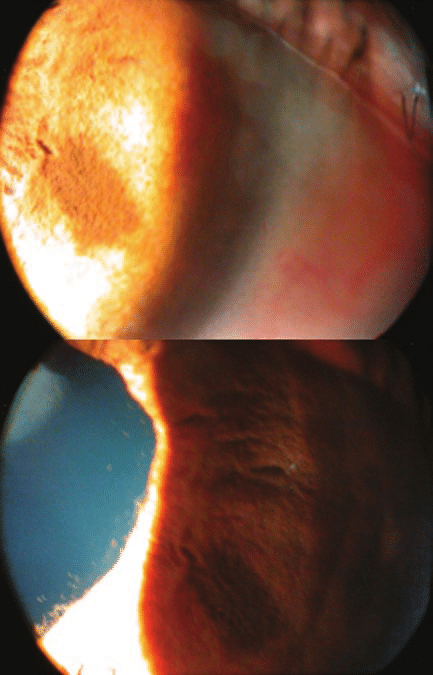

각막내피에 색소가 침착되고, 특히 각막 후면의 중앙부에 spindle shape 의 색소침착체인 Krukenberg spindle 이 보입니다.

전방각경 검사를 하면 섬유주 전반에 걸쳐

짙고 균일한 어두운 갈색의 색소띠가 관찰됩니다.